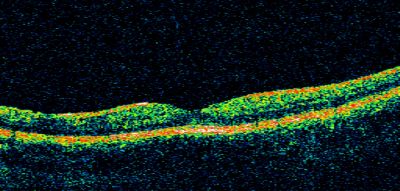

Basal Laminar Drusen - Cuticular Drusen - 19 Year Old with Lupus Nephritis

19-year-old.  She has a history of developing severe systemic lupus erythematosus in 2001.  She was in renal failure and had biopsy proven Class 2 lupus nephritis.  She is currently on Plaquenil 400 mg for six years, as well as Prednisolone orally, every other day. OD 20/20, OS 20/25.